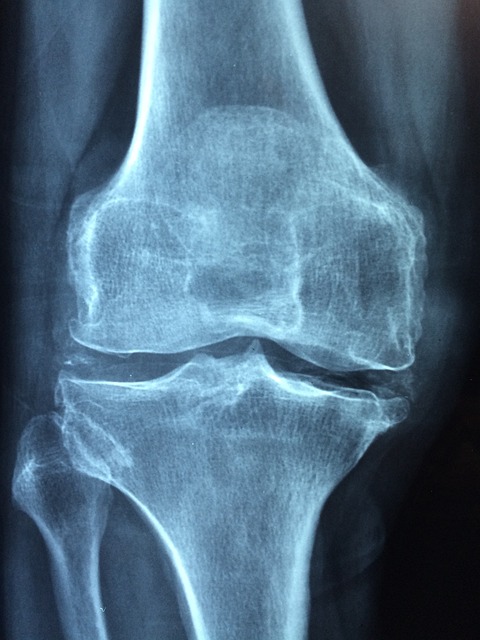

연골 연화증 증상

1. 관절 통증

관절 운동 시 통증이 심해집니다.

2. 관절 붓기

관절 주변에 부종이 발생할 수 있습니다.

3. 관절 움직임 제한

연골 손상으로 관절을 움직일 때 부자연스럽거나 제한적으로 움직여질 수 있습니다.

4. 감각 이상

관절에서 느껴지는 이상한 감각이나 불편함이 있을 수 있습니다.